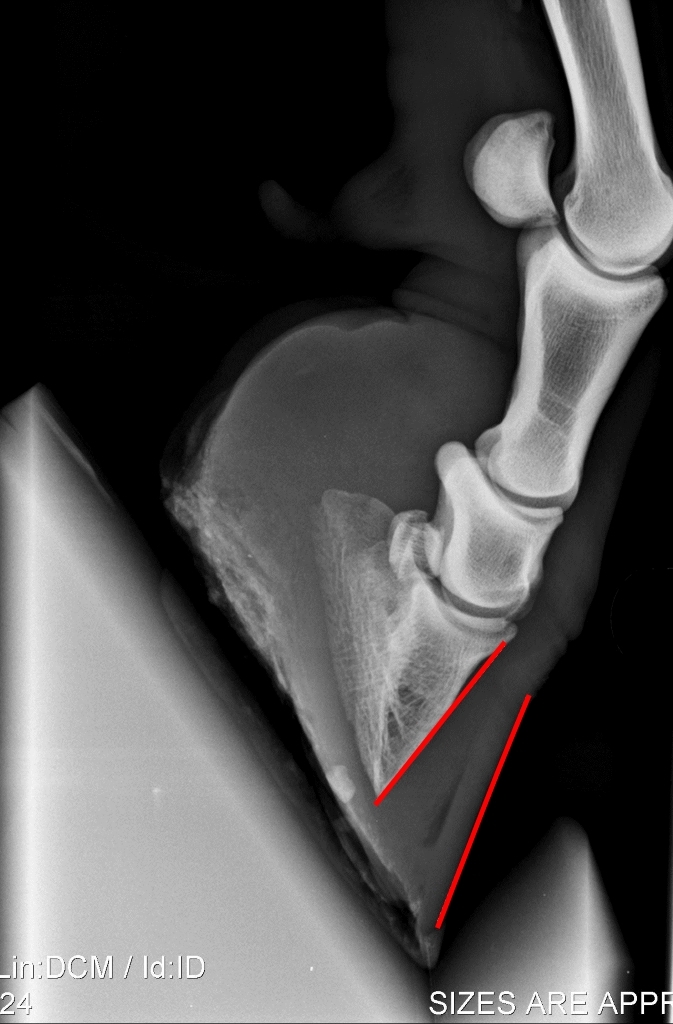

Als gevolg van de ontstoken lederhuid kan de verbinding tussen het hoefbeen en de hoefwand (deels) loslaten. Daardoor kan het hoefbeen gaan kantelen en er meer ruimte ontstaan tussen hoefbeen en hoefwand. Dit is het beste zichtbaar op röntgenfoto’s. De kanteling van het hoefbeen resulteert ook in een verbrede witte lijn. Op de lange termijn kan een kanteling van het hoefbeen zichtbaar blijven door een knikje in de hoefwand. Dat ontstaat doordat na een kanteling de hoefwand vanuit de kroonrand weer vlakker langs het hoefbeen af groeit terwijl de ontstane ruimte tussen hoefbeen en hoefwand verderop aanwezig blijft. In zeer ernstige gevallen kan de verbinding tussen hoefbeen en hoefwand zodanig verslechteren dat het hoefbeen niet alleen kantelt maar zelfs in zijn geheel gaat zakken binnen de hoefcapsule. Dit is een zeer ernstige complicatie waarbij het zover kan gaan dat het hoefbeen door de zool heen drukt, een zoolbreuk.

Zijdelingse röntgenopnames van ondervoeten, de hoefwand en het hoefbeen zijn met rode lijnen geaccentueerd. Links een normale ondervoet zonder gekanteld hoefbeen. Rechts een röntgenopname van een vrij ver gekanteld hoefbeen.